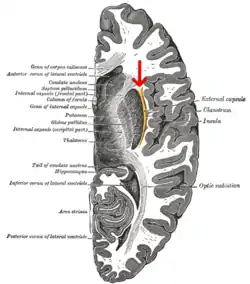

Horizontal section of right cerebral hemisphere. (external capsule shown in orange, indicated by red arrow.)

External capsule

The external capsule is a series of white matter fiber tracts in the brain. These fibers run between the most lateral (toward the side of the head) segment of the lentiform nucleus (more specifically the putamen) and the claustrum.